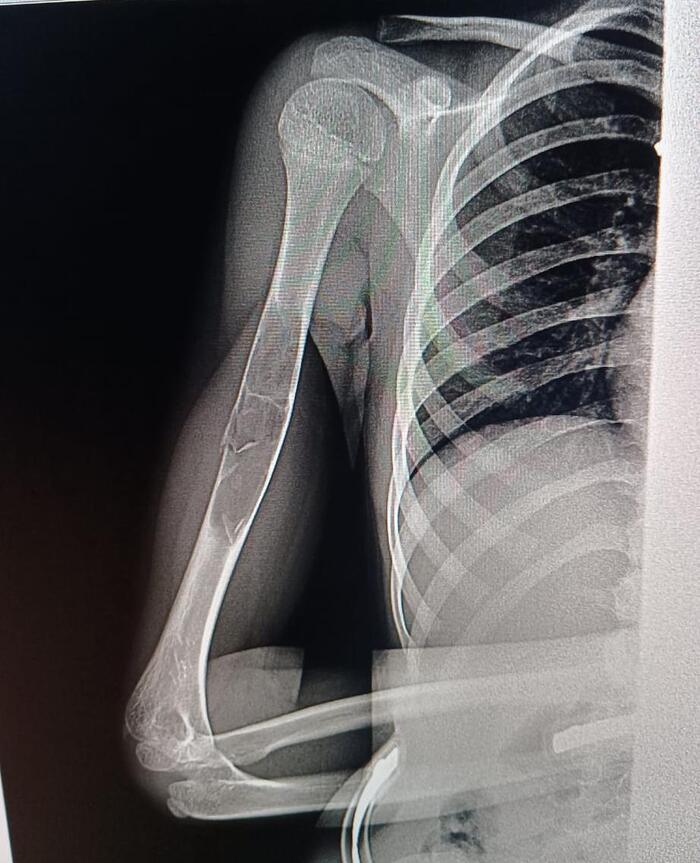

Петербург. Девочка, почти 9 лет, легкий сколиоз. Падение с велосипеда, RG руки, результат

Имеем патологический перелом, причина - предположительно, фиброзная дисплазия или аневризмальная киста кости.

Рекомендованный план лечения: 6 недель в гипсе по турнеру, полное заживление перелома и образование костной мозоли, потом КТ и дифдиагностика, подготовка и операция по удалению всего образования.

Врачи говорят, что зоны роста почти не задеты, есть шанс полного восстановления здоровья и полноценной дальнейшей жизни.

Нужно исключить множественность образований. Соответственно, нужна денсинтометрия или RG всего ребёнка. При ФД наблюдается поражение трубчатых костей: большеберцовой, бедренной, малоберцовой, плечевой, лучевой и локтевой. Из плоских костей чаще страдают кости таза, кости черепа, позвоночник, ребра и лопатка. Нередко выявляется поражение костей кистей и стоп. При АКК наиболее частая локализация: кости позвоночника, затем дистальный отдел бедренной и проксимальные отделы большеберцовой и плечевой костей, кости таза.

Что нужно для 100% исключения более страшных вариантов? Надеюсь, что врачи правы, и сие не злокачественное, но дифдиагностика: Остеофиброзная дисплазия, гигантоклеточная репаративная гранулёма кости, болезнь Педжета, высокодифференцированная центральная остеосаркома, паростальная остеосаркома.